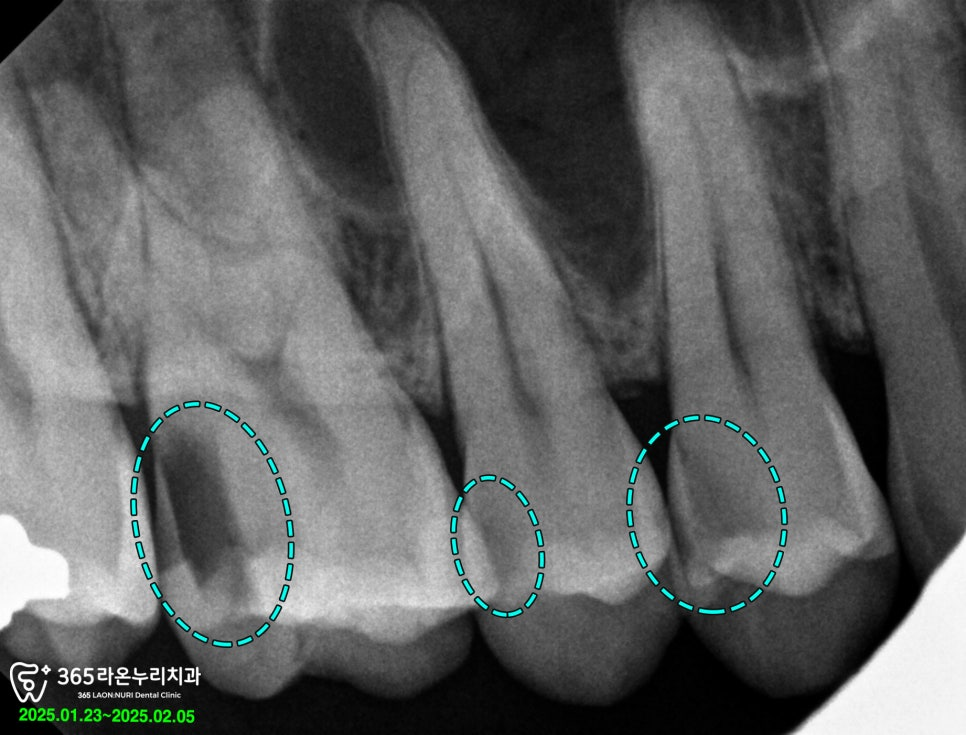

현재로써는 이미 신경과 가깝게

진행되었기 때문에 지속적인

자극으로 통증이

나타나고 있던 상황이었습니다.

이에 세교동 치과 에서는

옆면에 나타난 충치까지

깔끔하게 제거한 다음

신경치료 및 레진 코어를

진행하기로 결정 했습니다.